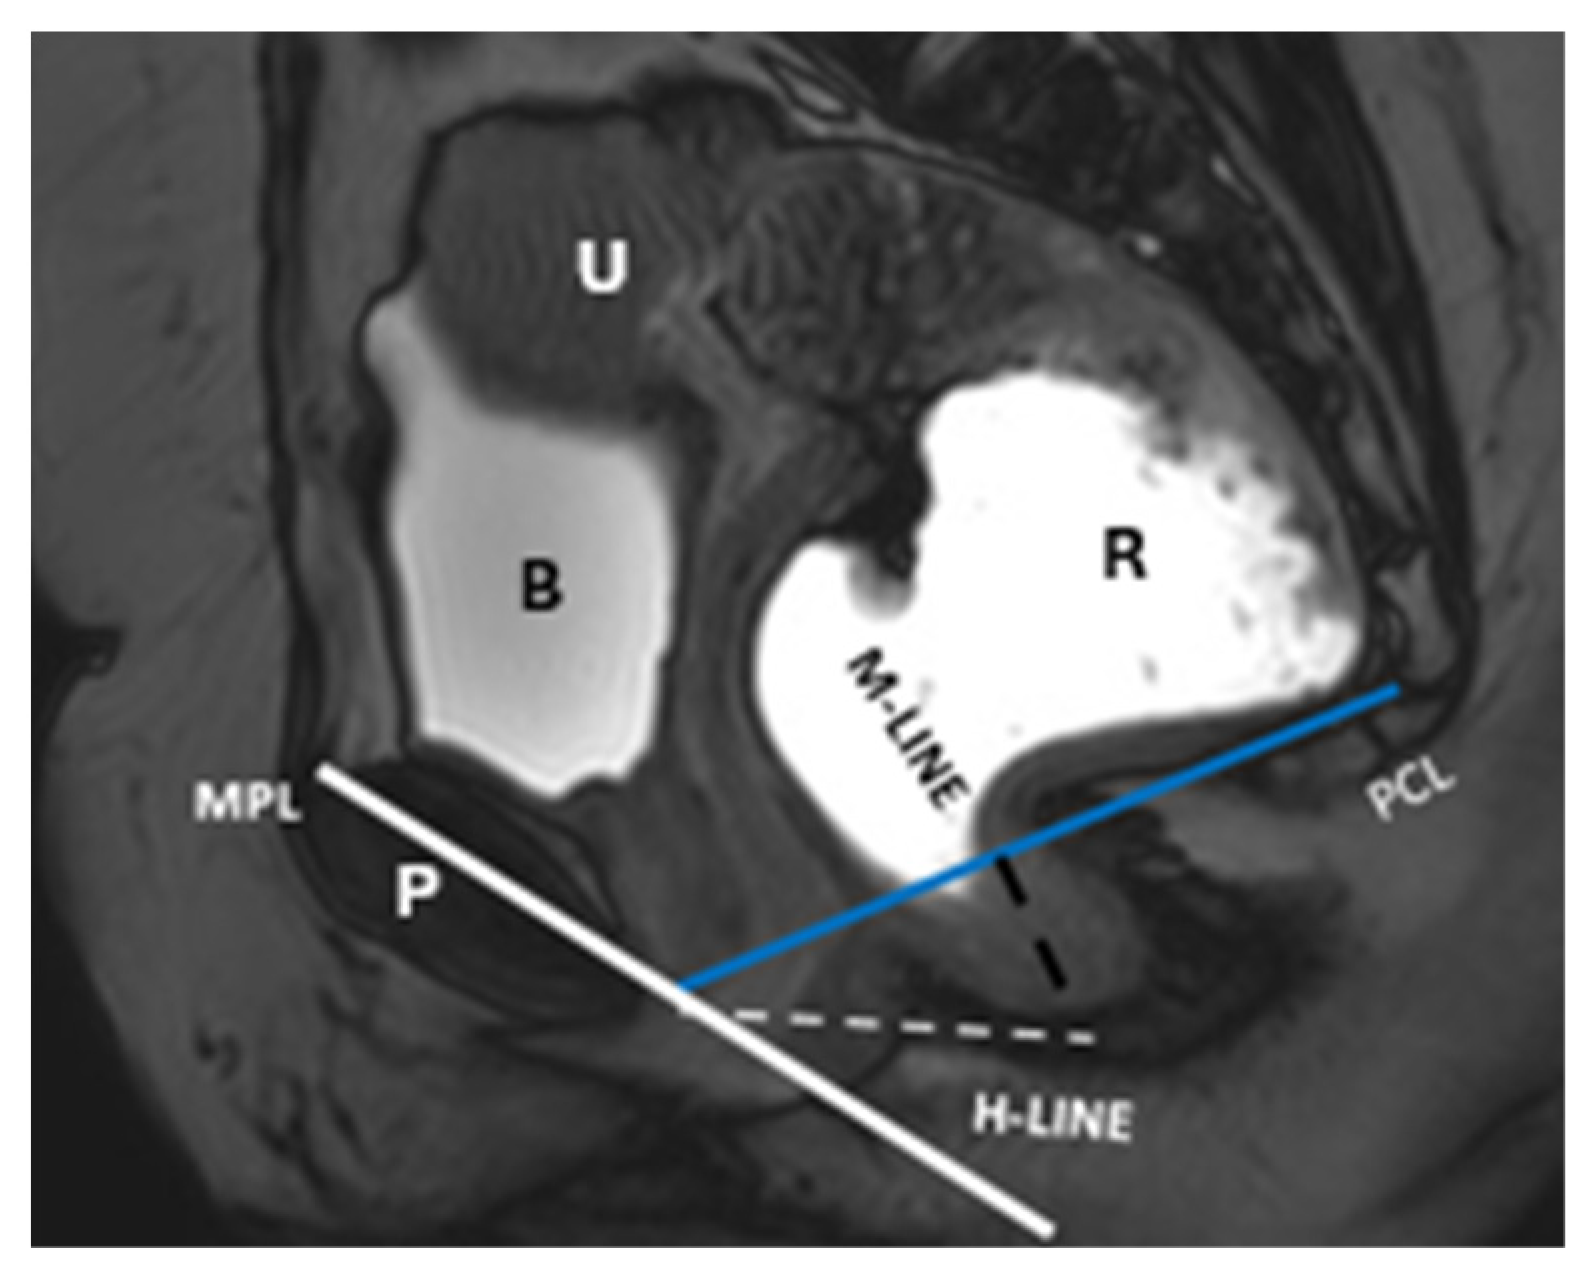

| Component/Reference Line | Definition | Role in HMO System | Normal Range/Severity/Staging |

|---|---|---|---|

| Pubococcygeal Line (PCL) | Line from the inferior pubic border to the last coccygeal joint | Baseline for measuring organ descent | PCL Compartment Staging Stage 0: Above PCL Stage I: Descent <3 cm below PCL Stage II: Descent 3–6 cm below PCL Stage III: Descent >6 cm below PCL Stage IV: Complete organ prolapse |

| Mid-pubic Line (MPL) | Line drawn through and caudad through the axis of the mid-pubic symphysis on sagittal MRI | Used to assess pelvic organ prolapse (POP); a 90° angle is measured between MPL and the bladder, vaginal vault, and anterior anorectal junction | MPL Compartment Staging Stage 0: >3 cm above MPL or TVL −2 cm Stage I: 1 cm above ≤ X ≤ 1 cm below MPL Stage II: 1 cm above ≤ X ≤ 1 cm below MPL Stage III: ≥1 cm below MPL Stage IV: Complete organ prolapse |

| H Line (Hiatal Line) | Distance between the inferior pubic border and the anorectal junction | Assesses puborectal hiatus (anteroposterior dimension during straining) | POP Grade Hiatal Enlargement Normal: <6 cm Mild: 6–8 cm Moderate: 8–10 cm Severe: >10 cm |

| M Line (Muscle Line) | Perpendicular line from the PCL, measuring organ descent | Evaluates posterior pelvic organ descent | Pelvic Floor Descent Normal: <2 cm Mild: 2–4 cm Moderate: 4–6 cm Severe: >6 cm |

| Anorectal Angle | Angle between the posterior distal rectum and the anal canal’s central axis | Reflects the levator ani muscle function during contraction | 108–127° at rest, decreases by 15–20° during contraction |